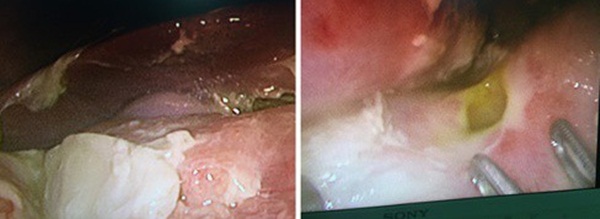

Hình ảnh lỗ thủng và giả mạc.

Các bác sĩ khoa Ngoại Nhi đã tiến hành phẫu thuật nội soi kết hợp truyền máu hồi sức cho cháu bé. Ghi nhận tổn thương trong mổ: Có 01 lỗ thủng tại mặt trước của hành tá tràng kích thước khoảng 0.7x0.7 cm, bờ lỗ thủng mềm, dễ rách, kèm theo nhiều giả mạc, dịch đục trong ổ bụng. Bệnh nhân đã được phẫu thuật nội soi khâu lỗ thủng hành tá tràng, lau rửa sạch ổ bụng. Sau 7 ngày điều trị tại khoa Ngoại nhi, toàn trạng trẻ ổn định, ăn uống bình thường và được xuất viện.